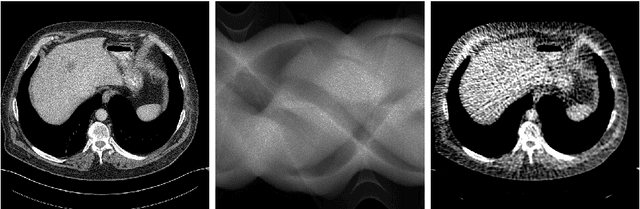

Abstract:Model-based learned iterative reconstruction methods have recently been shown to outperform classical reconstruction methods. Applicability of these methods to large scale inverse problems is however limited by the available memory for training and extensive training times. As a possible solution to these restrictions we propose a multi-scale learned iterative reconstruction algorithm that computes iterates on discretisations of increasing resolution. This procedure does not only reduce memory requirements, it also considerably speeds up reconstruction and training times, but most importantly is scalable to large scale inverse problems, like those that arise in 3D tomographic imaging. Feasibility of the proposed method to speed up training and computation times in comparison to established learned reconstruction methods in 2D is demonstrated for low dose computed tomography (CT), for which we utilise the data base of abdominal CT scans provided for the 2016 AAPM low-dose CT grand challenge.

Abstract:Characterizing statistical properties of solutions of inverse problems is essential for decision making. Bayesian inversion offers a tractable framework for this purpose, but current approaches are computationally unfeasible for most realistic imaging applications in the clinic. We introduce two novel deep learning based methods for solving large-scale inverse problems using Bayesian inversion: a sampling based method using a WGAN with a novel mini-discriminator and a direct approach that trains a neural network using a novel loss function. The performance of both methods is demonstrated on image reconstruction in ultra low dose 3D helical CT. We compute the posterior mean and standard deviation of the 3D images followed by a hypothesis test to assess whether a "dark spot" in the liver of a cancer stricken patient is present. Both methods are computationally efficient and our evaluation shows very promising performance that clearly supports the claim that Bayesian inversion is usable for 3D imaging in time critical applications.